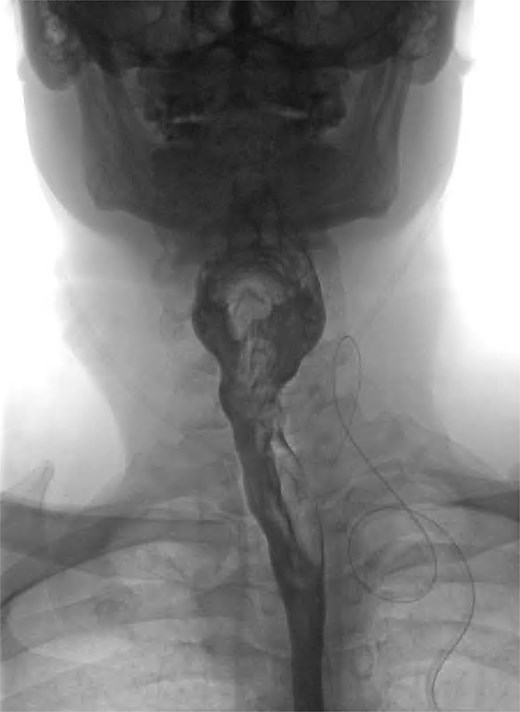

We present the case of a 57-year-old male patient who presented with dysphagia, regurgitation of undigested food, alongside a globus sensation. He had no significant medical history. He underwent a fluoroscopic swallow study, which revealed an anterolateral pharyngeal diverticulum consistent with a KJD with a neck of 5 mm and a length of 25 mm (Fig. 1). Given his symptoms, operative management was undertaken in which an incision was made along the medial border of the sternocleidomastoid. The platysma was divided, and dissection performed down to the level of the thyroid membrane with preservation of strap muscles. The left recurrent laryngeal nerve (RLN) was identified and preserved (Fig. 2). The esophageal diverticulum and sac were isolated from surrounding structures, and the neck was ligated using a 2/0 Vicryl prior to being excised. The ligation site was oversewn with 3/0 Vicryl. A drain was left, and the incision was closed in layers. Post-operatively, the patient underwent fluoroscopic swallow study, which did not show a leak or residual diverticulum, and after removal of the drain, the patient was discharged home day 1 postoperatively (Fig. 3).

Coronal view of fluoroscopic swallow showing Killian-Jamieson esophageal diverticulum labeled A.